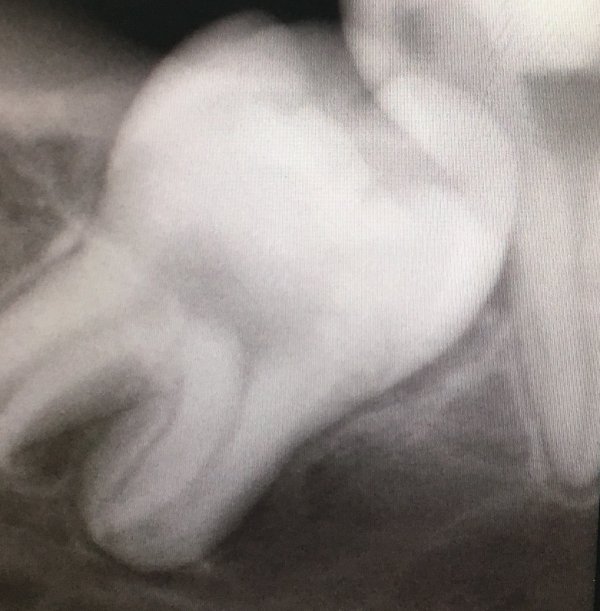

При подозрении на ретенцию зуба следует обязательно сделать рентгенологическое исследование. Поставить правильный диагноз можно только при наличии рентгеновского снимка, на котором видны сформированные, но непрорезавшиеся зачатки зубов.

При полной ретенции зуб полностью покрыт десной, он не обнаруживается ни при осмотре, ни при пальпации или исследовании полости рта при помощи стоматологического зонда. В этом случае обнаружить зачатки зубов можно только при рентгенологическом исследовании.